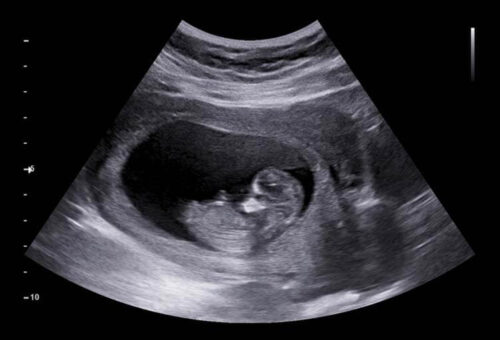

Wat je vervolgens op het beeldscherm ziet, is een weergave in zwart, wit en diverse grijstinten. Deze kleuren vertellen de specialist iets over de dichtheid van het weefsel:

- Botten kaatsen het ultrageluid heel sterk terug en zien er daardoor spierwit (echodens) uit.

- Waterige gebieden, zoals je volle blaas of het vruchtwater waarin je baby rondzwemt, laten juist al het geluid door en weerkaatsen niets. Deze delen worden gitzwart (echolucent) afgebeeld.

- Weefsels en organen, zoals de lever of longetjes, kaatsen het geluid wisselend terug en geven een gespikkeld, grijs beeld (echogeen).

Naast het onderscheid tussen inwendig en uitwendig kijken, zijn er ook verschillende soorten echo’s op basis van de gebruikte beeldtechniek. De beelden die je waarschijnlijk het beste kent, zijn gemaakt met een 2D-echo (soms B-mode genoemd). Dit is het standaard zwart-witbeeld in de lengte en breedte, wat in de verloskunde de vertrouwde basis vormt voor het medisch beoordelen van de ontwikkeling van je baby. Soms hoor je ook over een 3D-echo of een 4D-echo. Een 3D-echo zendt signalen uit om een ruimtelijk, stilstaand beeld te maken, en bij een 4D-echo wordt de dimensie ’tijd’ daaraan toegevoegd, waardoor je een bewegend ruimtelijk beeld van je kindje ziet. Hoewel we dit vaak kennen van pretecho’s, zet een arts een 3D-echo soms ook medisch in om bijvoorbeeld een vermoeden van een gespleten lipje (schisis) veel gedetailleerder te kunnen bekijken.